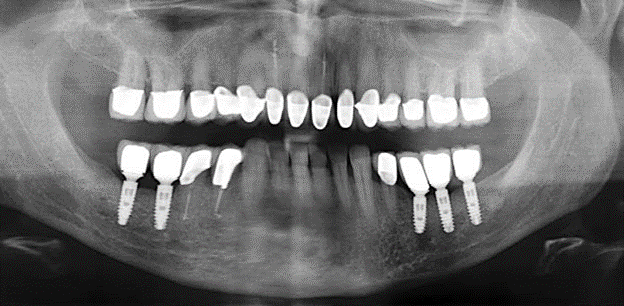

Aufgrund der bestehenden parodontalen Vorerkrankung erfolgte die unterstützende Parodontaltherapie (UPT) in den ersten Jahren in einem DreiMonatsIntervall. Dabei zeigte die Patientin eine hohe Motivation und gute Compliance. Bei den jährlich erhobenen Sondierungsbefunden zeigten sich stabile parodontale Verhältnisse mit einem BOPIndex unter fünf Prozent. Aufgrund der stabilen parodontalen Situation und der guten Mitarbeit der Patientin wurde ab dem sechsten Jahr der prothetischen Funktionsphase das Recallintervall auf halbjährlich umgestellt. Auch mit diesem veränderten Recallintervall zeigten sich bei der jeweils jährlichen Aufnahme des Parodontalstatus stabile parodontale Verhältnisse, ohne Zunahme der Sondierungstiefen und einem BOPIndex unter fünf Prozent (Abb. 2a und b).

Abb. 2: Die jährlich erhobenen Sondierungstiefen zeigen auch bei einem halbjährlichen Intervall der UPT keine Tendenz für eine Zunahme und einem BOP-Index unter fünf Prozent bei weitestgehend entzündungsfreien parodontalen Verhältnissen. a) PAR-Status 2011 (fünf Jahre prothetische Funktionsphase). b) PAR-Status 2016 (zehn Jahre prothetische Funktionsphase).